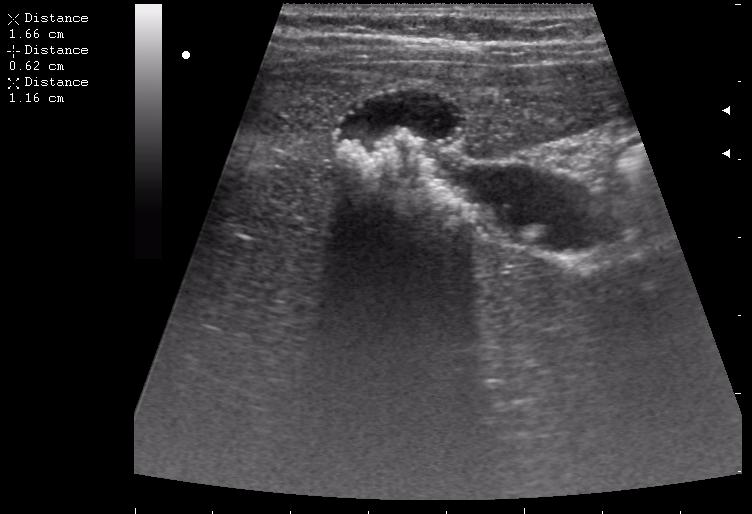

железный дрын вошел в правую подвздошную область, остановился в капсуле печени.

>желтой стрелкой - это левый надпочечник?

Похоже.

Он обычно располагается больше кнутри от верхнего полюса почки и может досигать ее ворот.

Надежнее визуализировать ЛН из позиции, которую я показывал в известной Вам теме.